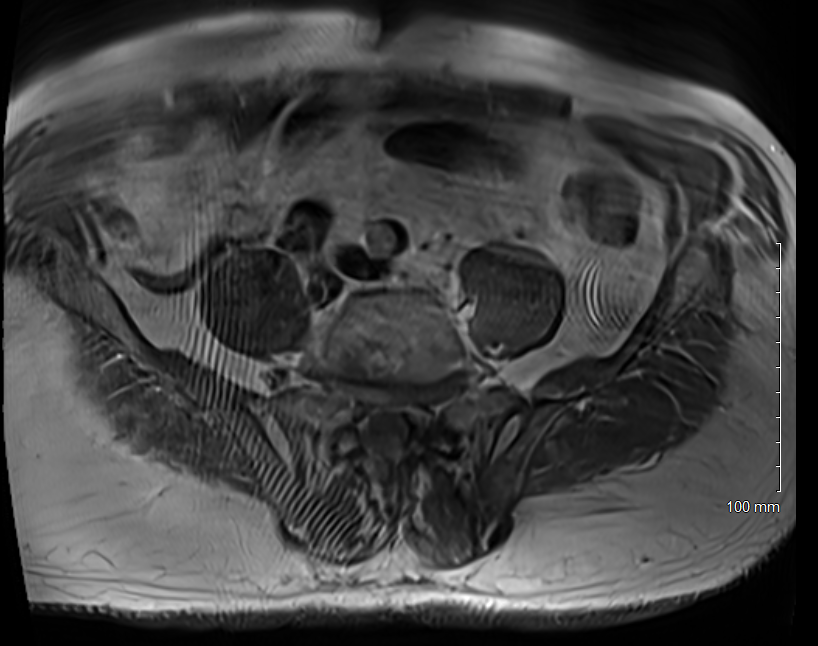

We saw this artifact on several slices of a T1weighted scan (tse2d1_3) obtained on a 3T Siemens Skyra. I suspect the subject's arms and hands are by their side and as the FOV is pretty small, 320 mm, they may be outside the FOV even with oversampling. Any other thoughts to explain the wavey lines?